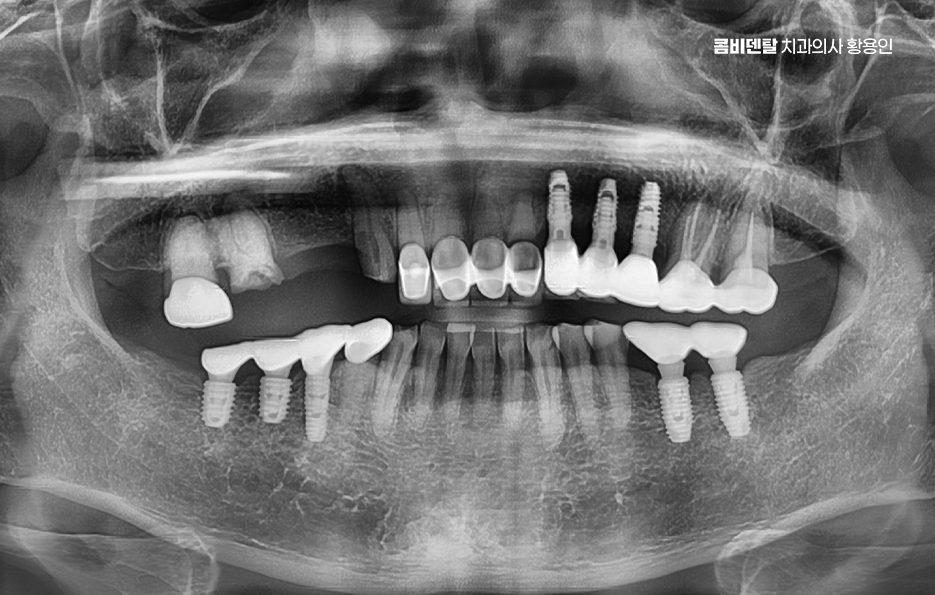

이러한 문제를 막기 위한 효과적인 방법이 바로 임플란트 치료로 어금니 임플란트를 계획할 때는 먼저 잇몸뼈 상태를 정밀하게 확인해야 하며 3D CT 촬영을 통해 뼈의 높이와 두께, 그리고 임플란트를 심을 수 있는 공간을 세밀하게 분석해야 하며 위턱 어금니 같은 경우 상악동이라는 빈 공간이 바로 위에 있어서, 치아가 빠지고 나면 그 공간이 아래로 내려와 임플란트를 심을 자리가 부족해지는 경우가 많고 아래턱 어금니는 하치조신경이라는 중요한 신경이 지나가기 때문에, 신경을 피해서 정확한 위치와 각도로 식립하는 계획이 필요할 수 있어요

결론적으로 어금니 임플란트를 하지 않고 방치하면, 단순히 어금니 하나의 문제가 아니라 전체 교합, 반대편 치아, 나아가 턱관절 기능과 소화 건강까지 영향을 주게 되기 때문에, 가능한 빠르게 치료를 결정하는 것이 장기적으로 더 많은 비용과 시간을 절약하는 방법이 되는 거예요. 특히 뼈가 아직 충분하고, 주변 치아가 건강할 때 임플란트를 진행하면 예후도 좋고, 추가적인 뼈이식이나 부가 수술 없이도 비교적 간단하게 치료가 가능한 경우가 많아서 어금니 상실 후에는 임플란트 치료와의 연계를 잘 고려해서 치료 계획을 늦지 않게 세우시길 바라고 있어요